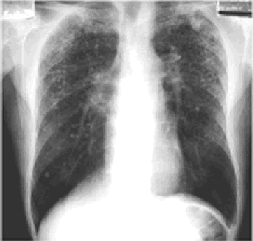

la radiographie pulmonaire